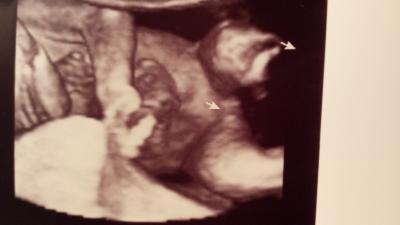

Welches Geschlecht seht ihr :-)

Bild zu Was meint ihr :-) - Schwanger - wer noch? Rund um die Schwangerschaft

Mädchen :) Die zwei helleren Striche müssten doch die schamlippen sein

Es sieht so aus als wäre noch was zwischen den Beinen also ein junge.

Das ist ein mädchen! Mein kleiner jungen hatte sein outing in der 18. Ssw und da war bedeutend mehr zwischen den beinen ;)

Laut Fa zu 100% ein Mädel :-) also die Mehrheit hatte recht :-)